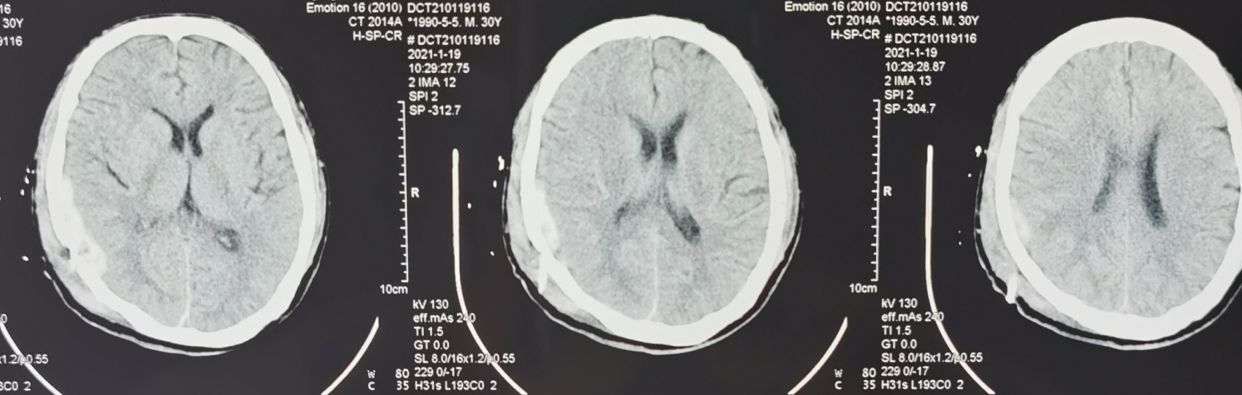

术后复查CT如下,进一步确认了此为硬膜下血肿,不是硬膜外血肿!

1月19号复查CT,硬膜下血肿显著减少!